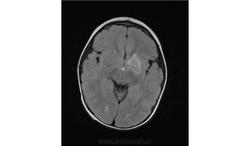

Ребенок 2 года, заболели в середине декабре, гемипорез, к сожелению не могу ни как с контрасном исследованеим здесь загрузить но накапление контрасного вещества нет, спосибо за помочь!!!!!!!

Предположу гипоксически-ишемические изменения с диапедезным кровоизлиянием. Но они чаще двусторонние.